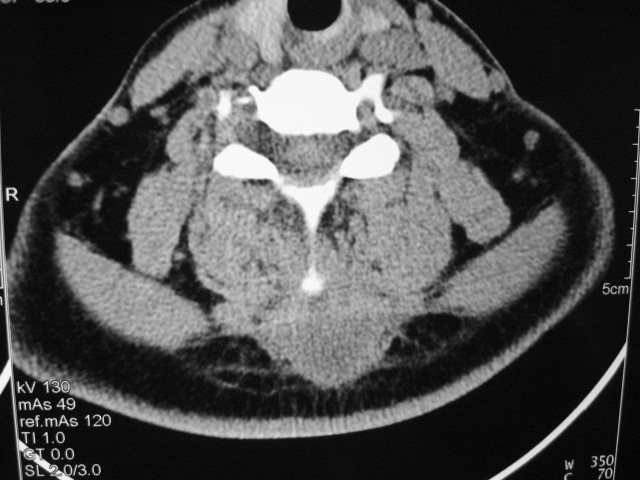

女,46岁,发现颈后区肿块3月余.

颈后软组织肿块,内可见坏死区及点状钙化,邻近颈椎棘突可见破坏,邻近肌间隙模糊,肿块周围脂肪间隙可见索条状影。

考虑:1)感染,结核可能;

2)肿瘤不能排除。